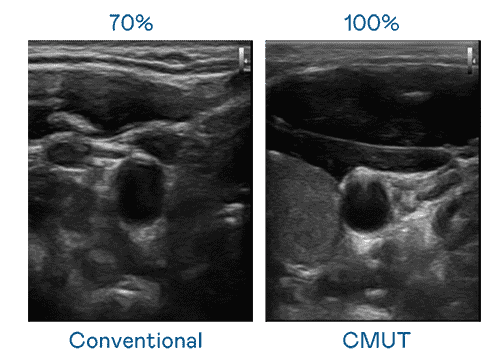

CMUT 技术是一种用电容式微机电元件来产生超音波讯号的技术。。。与传统 PZT 压电式技术相比,,,,CMUT 频宽增加 30%,,,,更宽频的超音波讯号让影像解析度大幅提升,,,是实现高影像品质医疗超音波扫描、、、促进精准医疗发展的关键技术。。

大频宽带来超清晰影像

超音波影像的解析度高低,,首先取决于探头能发出的讯号频宽。。。。万利 CMUT 可提供高清晰的超音波讯号,,提供高频宽、、、高灵敏度、、影像纹理细节更高的超音波影像,,,协助医护人员缩短影像判读时间及利用精准的医疗影像进行诊断。。